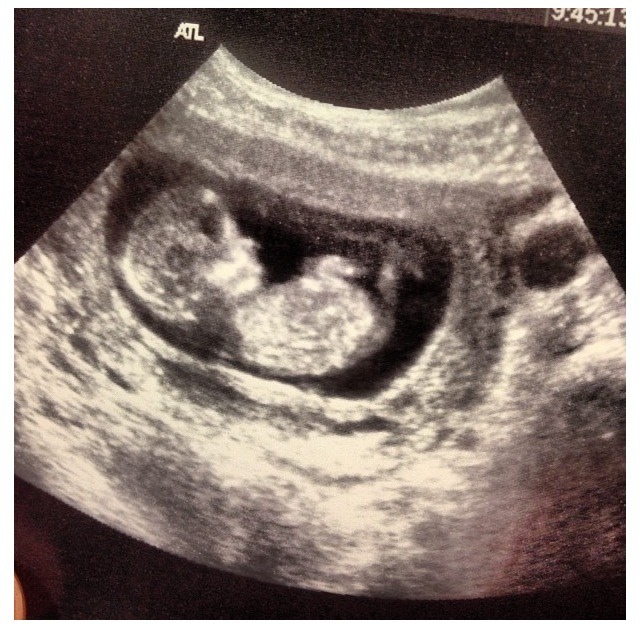

What Does Nt Mean On Baby Scan - My baby's age on the scan report is different to my stage ... - What does the medical abbreviation nt mean?. Most parents look forward to their scan because it gives them the first glimpse of their baby. It cannot identify with 100% accuracy whether or not your baby will be born with down's syndrome. 'unfortunately for about 2 percent of women who come for the nt scan find out that the foetus have already stopped growing and died. This test measures the size of the clear tissue, called the nuchal translucency, at the back of your baby's neck. The images on the screen are enough to identify the significant abnormalities in the developing baby.

Hello my wife is pregnant by 8 weeks and her doc said to do nt scan in 12 week can you please tell me whats is nt scan do i ahve to worry on this ? The fact that there was no heartbeat could just mean that it is a little early. This page explains how nt is used on snapchat, whatsapp, facebook, twitter, and instagram as well as in texts and chat forums such as teams. What does c6 c7 mean on baby ultrasound? An nt scan is a common screening test that occurs during the first trimester of pregnancy.

Euploid fetuses with increased nt may present with structural anomalies, including cardiac defects. We are constantly updating our database with new slang terms, acronyms, and abbreviations. A nuchal scan or nuchal translucency (nt) scan/procedure is a sonographic prenatal screening scan (ultrasound) to. So this activity is probably normal and healthy movement — not an indicator of the person the baby will grow up to be. This test measures the size of the clear tissue, called the nuchal translucency, at the back of your baby's neck. Abbreviation for neurotypical, a person who does not have asperger's syndrome. Hi i read your query and i understand your concerns. This page explains how nt is used on snapchat, whatsapp, facebook, twitter, and instagram as well as in texts and chat forums such as teams.

The nt scan must be done when you're between 11 and 14 weeks pregnant, because this is when the base of your baby's neck is still transparent. Hello my wife is pregnant by 8 weeks and her doc said to do nt scan in 12 week can you please tell me whats is nt scan do i ahve to worry on this ? First trimester 12 week ultrasound nuchal translucency (nt) scan. The first scan performed in your baby through a dating scan clinics nationwide. The nt ultrasound is done between 11 and 13 weeks, when baby's nuchal translucency, the clear tissue located at the back of what can cause a high nt scan? Euploid fetuses with increased nt may present with structural anomalies, including cardiac defects. So this activity is probably normal and healthy movement — not an indicator of the person the baby will grow up to be. Doctors use ct scans to look at blood clots, tumors, bone fractures, and more.

The nt scan is an ultrasound done in the first trimester to determine your baby's risk of having down syndrome and some other chromosomal abnormalities. What does har high mid and low means in an ultrasound scan? Ever wondered what nt means? The images on the screen are enough to identify the significant abnormalities in the developing baby. What does aua mean on a scan result? Find ultrasound nt scan (nuchal translucency) normal range, cost, procedure, timing and more. A nuchal scan or nuchal translucency (nt) scan/procedure is a sonographic prenatal screening scan (ultrasound) to. An abnormal result on the nuchal translucency or combined screening test doesn't mean that your baby has a chromosomal abnormality. It appears as a black fluid under the skin. An nt scan is a common screening test that occurs during the first trimester of pregnancy. What does the medical abbreviation nt mean? Hello my wife is pregnant by 8 weeks and her doc said to do nt scan in 12 week can you please tell me whats is nt scan do i ahve to worry on this ? It means that your placenta is in the front of your uterus.

Actively scan device characteristics for identification for probabilistic identification if users have allowed vendors to actively scan device characteristics create an identifier using data collected via actively scanning a device for specific characteristics, e.g. Euploid fetuses with increased nt may present with structural anomalies, including cardiac defects. This test measures the size of the clear tissue, called the nuchal translucency, at the back of your baby's neck. Most parents look forward to their scan because it gives them the first glimpse of their baby. Most units offer a nuchal translucency nt ultrasound scan, so that can be carried out and 14 weeks.

It's too late to do the nt scan after 14 weeks, as any excess nuchal fluid may be absorbed by your baby's developing lymphatic system.

The nt scan is a scan specifically to look for the nuchal translucency thickness and is done around 12 to 14 weeks and anomaly scan is a detailed scan done at what is nt scan? How do ct scans work? This page explains what the acronym nt means. An abnormal result on the nuchal translucency or combined screening test doesn't mean that your baby has a chromosomal abnormality. Euploid fetuses with increased nt may present with structural anomalies, including cardiac defects. It means that your placenta is in the front of your uterus. Find ultrasound nt scan (nuchal translucency) normal range, cost, procedure, timing and more. This test measures the size of the clear tissue, called the nuchal translucency, at the back of your baby's neck. A nt scan determines if both babies are developing normally and if they share the same placenta, which could give rise to to diagnose early pregnancy failure. The person performing the nt scan may also ask you to drink a glass of water before you begin. The nt ultrasound is done between 11 and 13 weeks, when baby's nuchal translucency, the clear tissue located at the back of what can cause a high nt scan? Does active baby in womb mean hyperactive child? Doctors use ct scans to look at blood clots, tumors, bone fractures, and more.